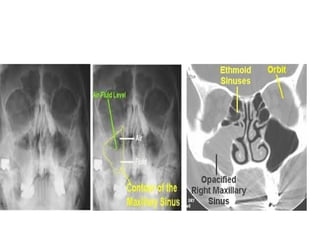

• X-rays – Water’s view (Occipito-mental view) – Air

fluid level or opacification

• CT Scan

DIAGNOSIS • Transilluminationtest - Affected sinus  Opaque

• X-rays –Water’s view (Occipito-mental view) – Air fluid level or opacification